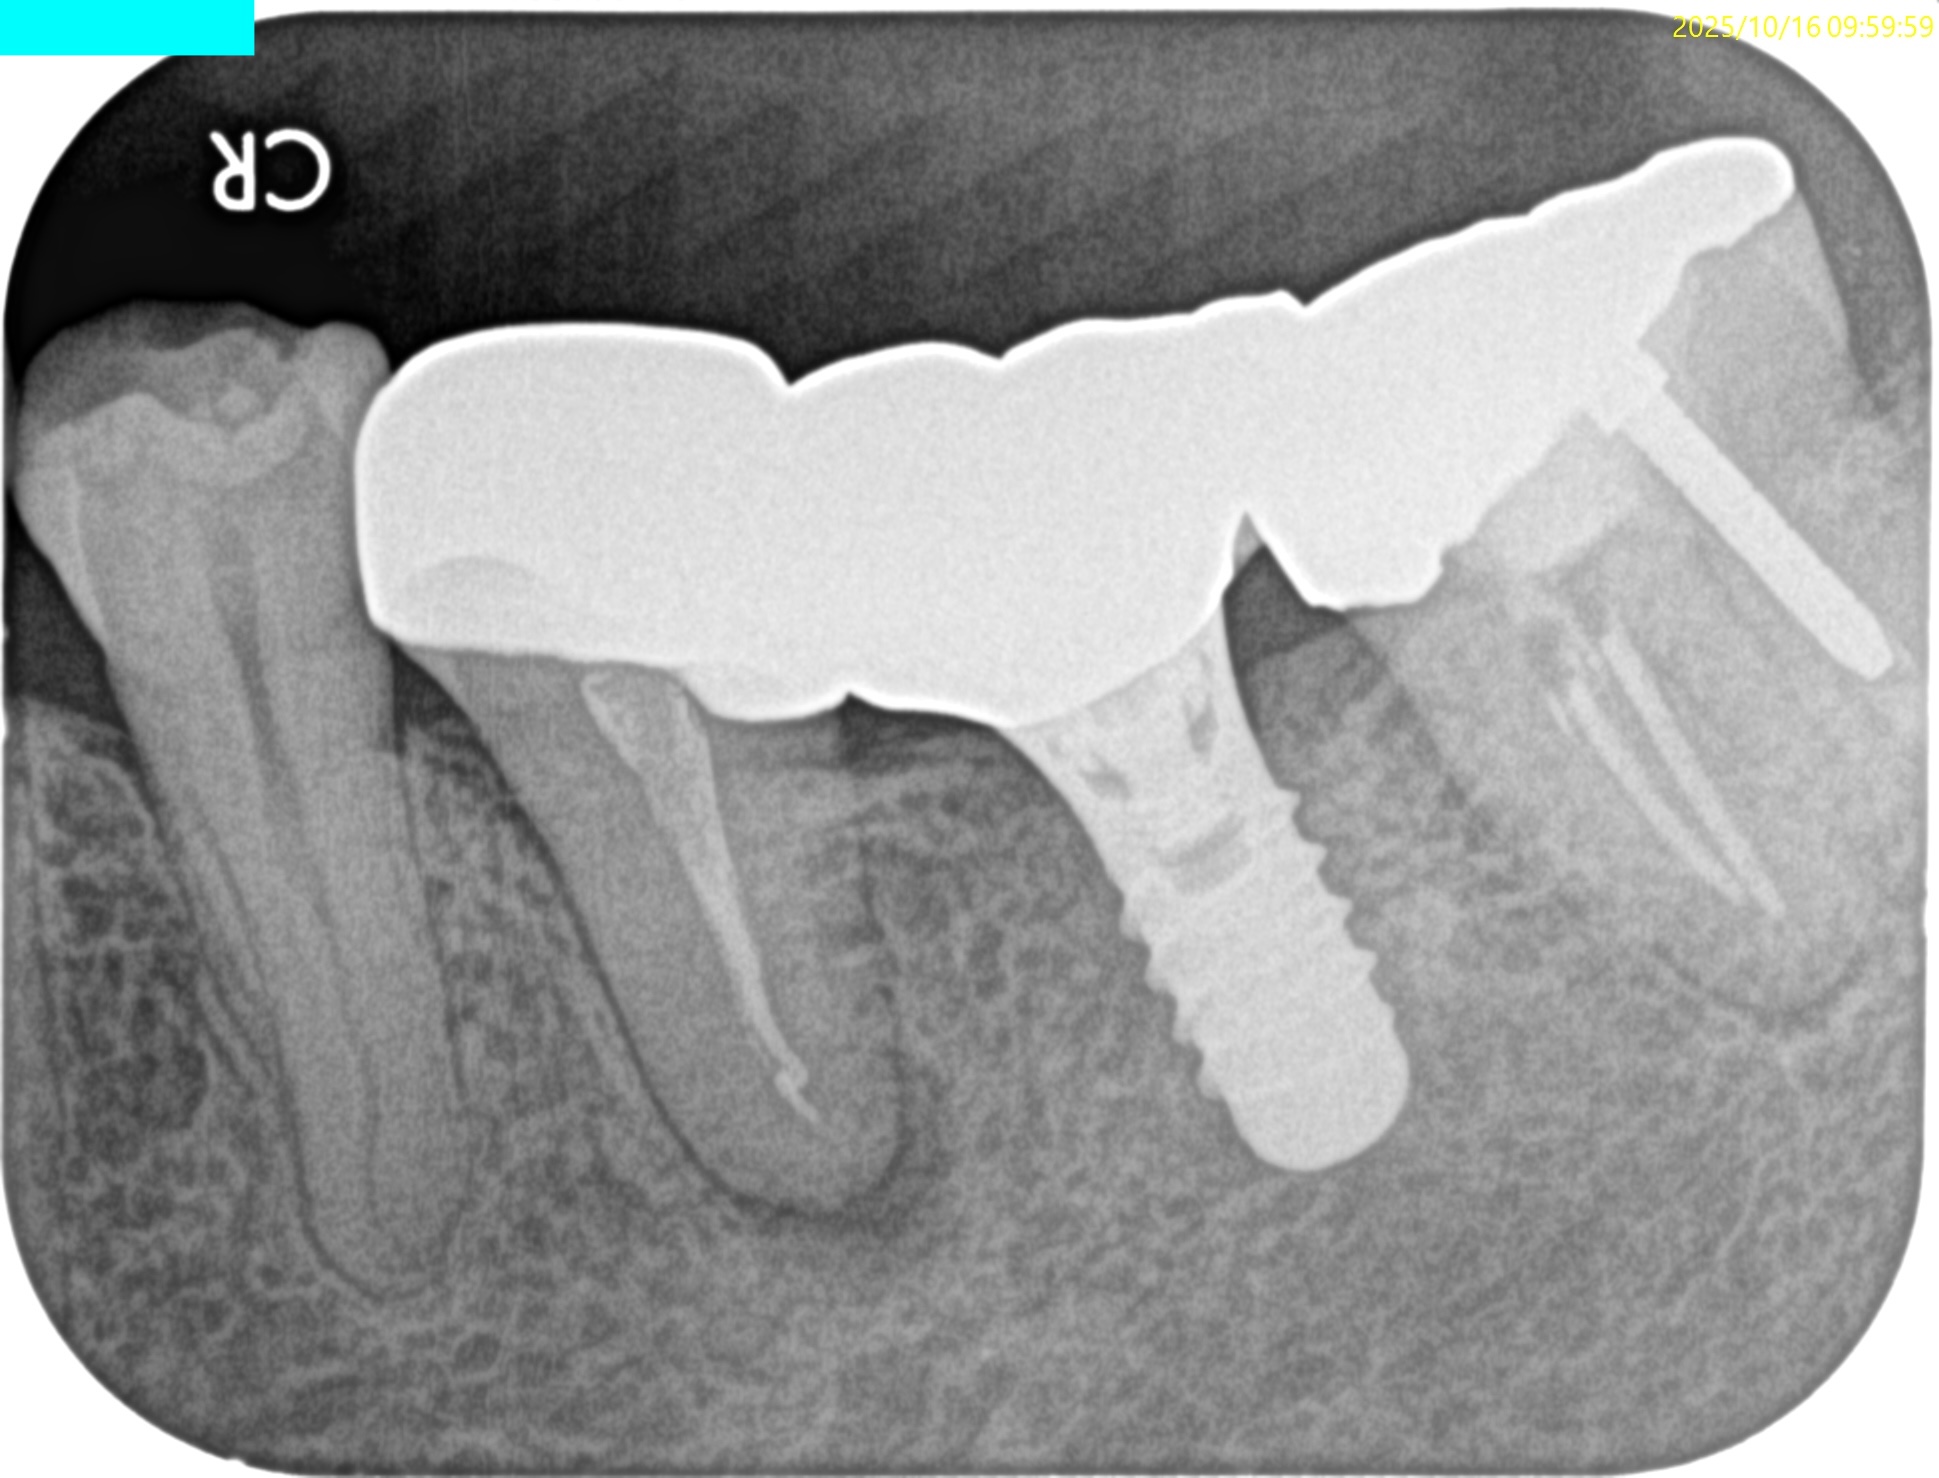

PAで状態確認し、問題がないことを確かめたのちに、

抜歯窩へ戻した。

術後のPA, CBCTは以下である。

問題はないだろう。